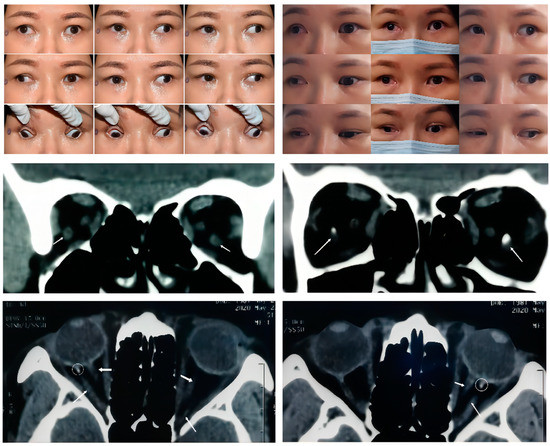

Figure 1. Upper panel: Nine gaze photographs of Case 1 showing a preoperative 65 PD alternating exotropia and a large A pattern strabismus. A moderate bilateral limitation of adduction and supraduction and mild bilateral limitation of infraduction were present in this case (left). Sixteen months after a second strabismus surgery (right), there was a slight improvement in the adduction of the right eye. A residual 25 PD exotropia and large A pattern strabismus remained. Middle Panel: Arrow in the coronal CT scan indicates a bilateral symmetric accessory extraocular muscle. The high-density image within the muscle suggests a local calcification just behind the posterior pole of the eyeball (the right picture). Bottom Panel: Thin arrow in the axial CT scan indicates that the accessory extraocular muscle in both eyes originat from the apex of the orbit and inserting into the posterior globe lies between the lateral rectus and optic nerve. Thick arrow: the optic nerve. Circle: local calcification within the muscle.

In this study, we distinguished four types of SEOM within the 12 cases reviewed. These categories were based on the origins and insertions as observed from the imaging results. Type 1 SEOM involves a discrete accessory EOM inserting into the sclera, which is well-defined and tends to be readily identified with imaging. Therefore, there have been many reports describing this type of SEOM. Type 1 SEOM tends to insert into the posterior globe beneath the optic nerve, especially the inferotemporal quadrant [4,5,7,12]. Valmaggia [5] reported on the case of a 6-year-old boy with a similar anomaly and elevation deficiency in the left eye but no subjective complaints; thus, no strabismus surgery was performed. A case mentioned by Dobbs et al. [4] was diagnosed as Duane syndrome, and the patient underwent lateral rectus recession at the age of 23 months. Then the remaining limited supraduction and globe retraction indicated the existence of SEOM. The CT scan identified bilateral tissue isodense to muscle that was inferolateral to the optic nerve, and the postoperative pathological examination suggested that the tissue nature was similar to a normal EOM. Case 1 (Figure 1) displayed continuous exotropia after a previous strabismus surgery performed elsewhere (details unknown). We observed a 65 PD exotropia and 5 PD right hypertropia in the primary gaze with a moderate limitation of bilateral adduction and supraduction as well as a mild limitation of bilateral infraduciton in adduction. Coronal and axial CT scans revealed a bilateral symmetric accessory muscular tissue coursing from the annulus of Zinn to insert into the inferolateral sclera posteriorly. Interestingly, there was muscular calcification proximal to the globe in Case 1, a finding which has not been reported in previous studies. Compared with the other case types in this study, the clear structure of the SEOM in type 1 showed a smaller correlation with the optic nerve, indicating that it had less impact on visual acuity.